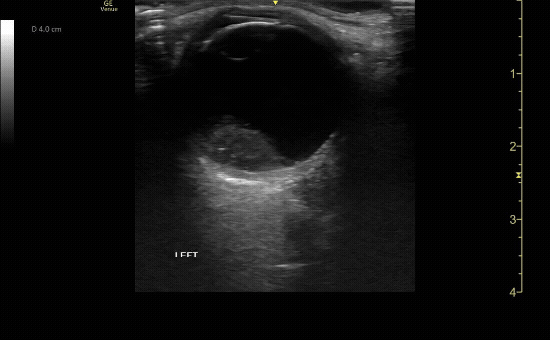

Mac off retinal detachment. Retina tethered at optic nerve.

c/o Melissa Hoshizaki, MD